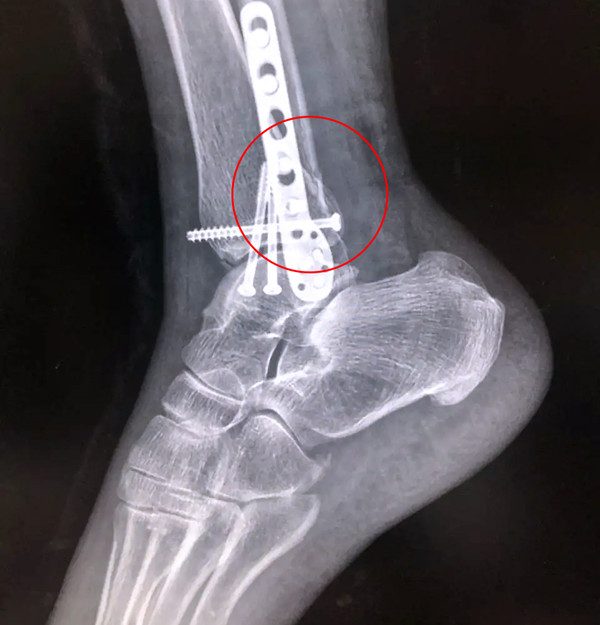

踝關節(jié)骨折在X影像上的表現(xiàn)有很多種。如內(nèi)踝骨折和外踝骨折,我們可以在影像上看到骨折處的骨折線是不連續(xù)的。還有后踝的骨折,內(nèi)踝、外踝、后踝聯(lián)合在一起發(fā)生的骨折,我們稱之為“三踝骨折”,這些都是在X影像上能夠顯示出來的。

三踝骨折